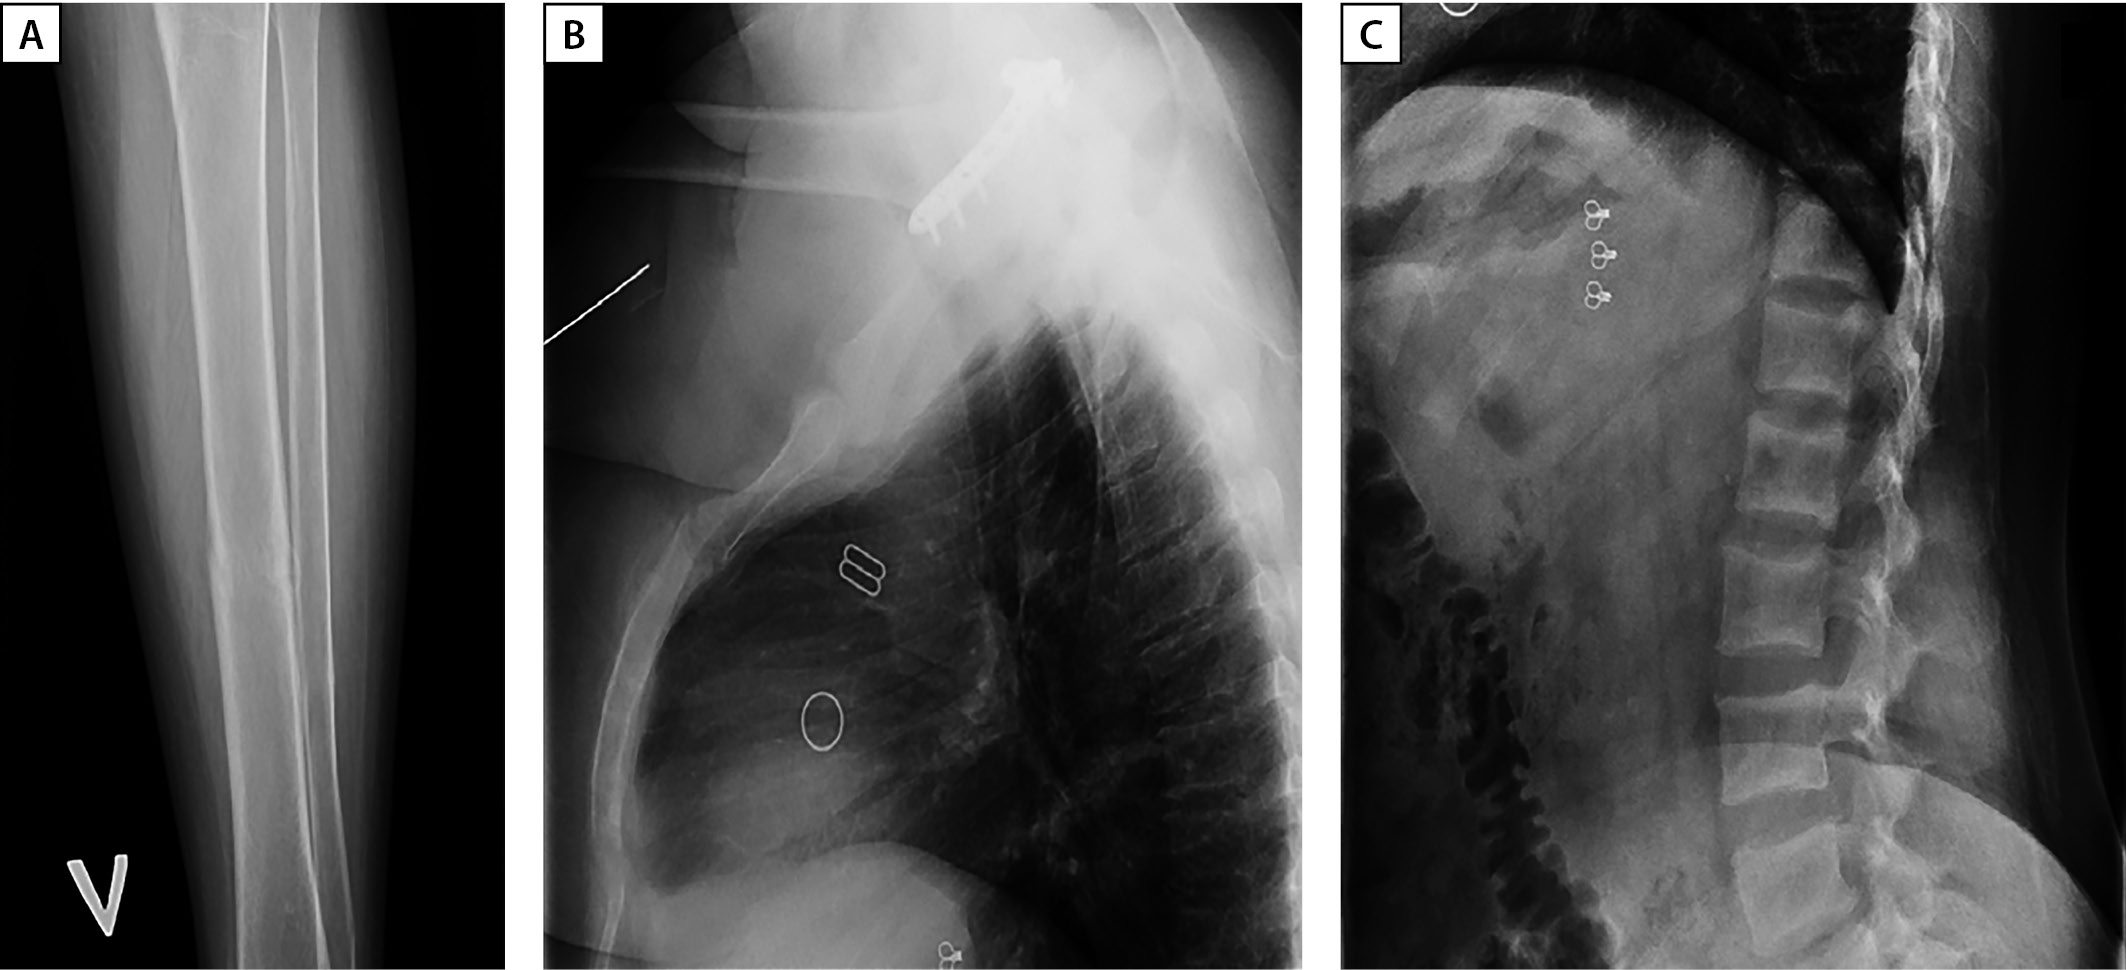

Также обращало на себя внимание значимое повышение сывороточных концентраций маркеров костного обмена: остеокальцин >300 нг/мл [ 11–43], С-концевые телопептиды коллагена I типа 3,61 нг/мл [ 0,3–0,57], щелочная фосфатаза 308 Ед/л [ 40–150]. Впервые проведена рентгенденситометрия, максимальное снижение минеральной плотности кости ниже ожидаемых возрастных значений до -2,8 SD по Z-критерию отмечалось в поясничном отделе позвоночника (L1–L4). Учитывая наличие в анамнезе перелома левой голени, проведена рентгенография: определялся консолидированный перелом в средней трети без смещения (см. рис. 1А). При рентгенографии грудного и поясничного отделов позвоночника данных за наличие компрессионных переломов не получено, однако визуализированы признаки начальной компрессии тел нескольких позвонков (рис. 1 В, С). По данным МСКТ визуализировались признаки фиброзно-кистозного остеита, консолидированных переломов 6 ребра справа и 6–8 ребер слева.

Рисунок 1. А — рентгенография левой голени в прямой проекции. Консолидированный перелом в средней трети без смещения. В — рентгенография грудного отдела позвоночника в боковой проекции. Гиперкифоз, умеренный остеохондроз, спондилез. Начальная компрессия тел Th7, Th8 позвонков по краниальной и каудальной площадкам преимущественно в передней трети позвонков (потеря до 5% массы). С — рентгенография поясничного отдела позвоночника в боковой проекции. Гиперлордоз, остеохондроз, ретролистез L4 и L1 на 2 мм. Начальная компрессия тел L5 (до 8% потери массы по каудальной площадке в задней трети позвонка), L3 ( до 5% в средней трети), L2 ( до 8% в средней трети) позвонков.

Figure 1. A — X-ray of the left leg in direct projection. Consolidated fracture in the middle third without displacement. C — X-ray of the thoracic spine in lateral projection. Hyperkyphosis, moderate osteochondrosis, spondylosis. Initial compression of the bodies of Th7, Th8 vertebrae along the cranial and caudal sites, mainly in the anterior third of the vertebrae (loss of up to 5% of the mass). C — radiography of the lumbar spine in lateral projection. Hyperlordosis, osteochondrosis, L4 and L1 retrolisthesis by 2 mm. Initial compression of the bodies of L5 (up to 8% weight loss along the caudal area in the posterior third of the vertebra), L3 (up to 5% in the middle third), L2 (up to 8% in the middle third) of the vertebrae.